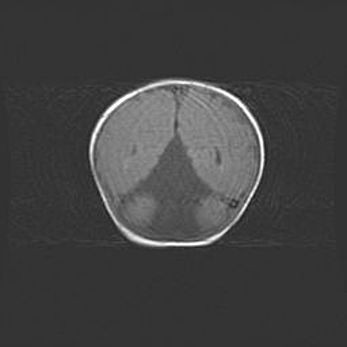

Лейкомаляция с кистозно-глиозной дегенерацией головного мозга.

Возраст: 2 месяца 25 дней

Вес: 6400 г

Окружность головы: 40 см

Срок гестации: 41 неделя

Лейкомаляцию относят к ишемически-гипоксическим повреждениям головного мозга, диагностируемым у новорожденных. При лейкомаляции в головном мозге обнаруживают очаги некроза, возникшие после тяжелой гипоксии и нарушения кровотока. В процессе морфогенеза очаги проходят три стадии: 1) развития некроза, 2) резорбции и 3) формирования глиозного рубца или кисты. Перивентрикулярная лейкомаляция (ПЛ) встречается примерно в 12% случаев среди новорожденных, обычно – у недоношенных детей, причем, частота ее зависит от массы, с которой младенец появился на свет. Наибольшее число малышей страдает лейкомаляцией, если масса при рождении 1500-2500 г.